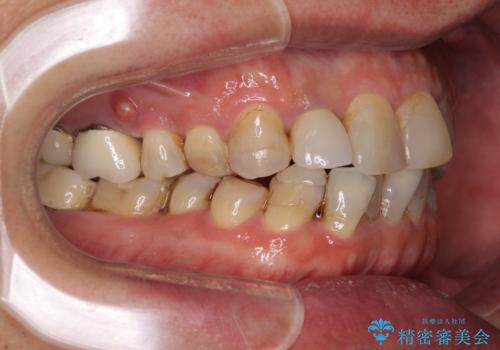

- 前歯のデコボコや、奥歯を咬んだときに痛みがあるとのことで来院された患者様です。

全体的に問題が多く、全てをしっかりと治療したいとのことでした。

全体的に中等度の歯周病と診断されたため、歯周外科処置やインプラントによる咬合回復から進めて行き、矯正治療による歯列改善を行った後にオールセラミッククラウンにて補綴することとしました。

矯正治療を希望して来院されましたが、歯周病を併発していたため、矯正治療開始前の処置が非常に多くなりました。特に歯槽骨の再生治療を行ったため、外科処置後の静置期間が長くなり、4年弱の治療期間となりました。